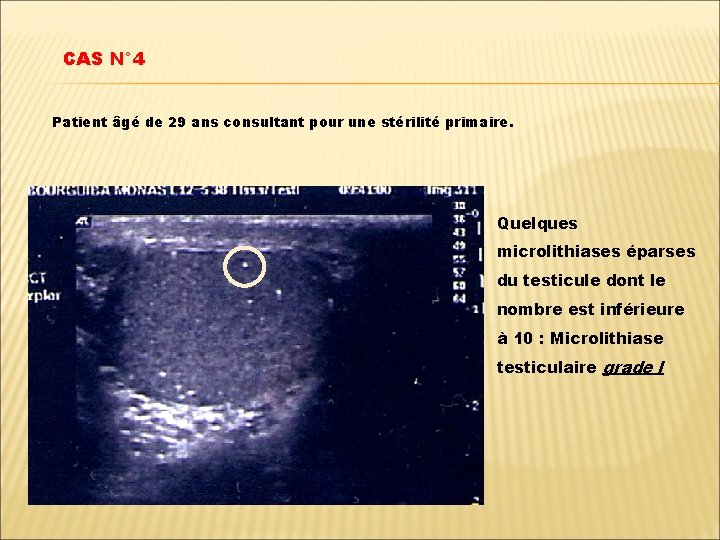

CAS N° 4 Patient âgé de 29 ans consultant pour une stérilité primaire. Quelques microlithiases éparses du testicule dont le nombre est inférieure à 10 : Microlithiase testiculaire grade I